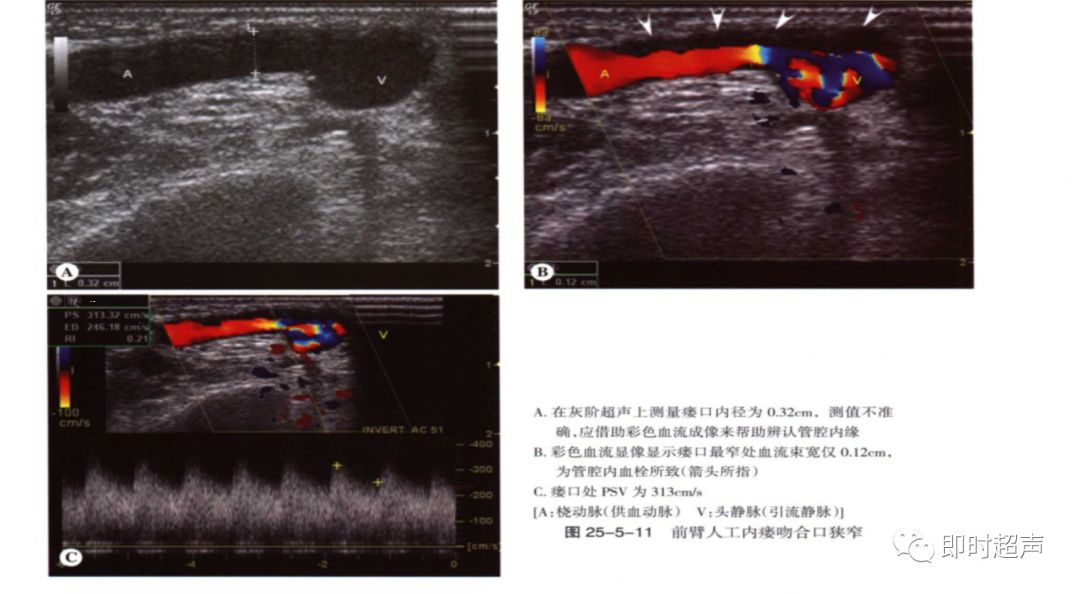

狭窄:狭窄大多发生于吻合口及静脉流出道。

超声表现:多普勒分析:狭窄处直接征象:PSV>4m/s(直径狭窄率50%以上),间接征象:供血动脉或肱动脉呈高阻波形,血流量减少。

(2)吻合口狭窄:分别测量吻合口处PSV及其上游2cm处动脉PSV,计算比值, ≥3.0时斟酌吻合口狭窄。

吻合口内径正常约3-5mm,若小于2.5mm,血流异常斟酌吻合口狭窄。